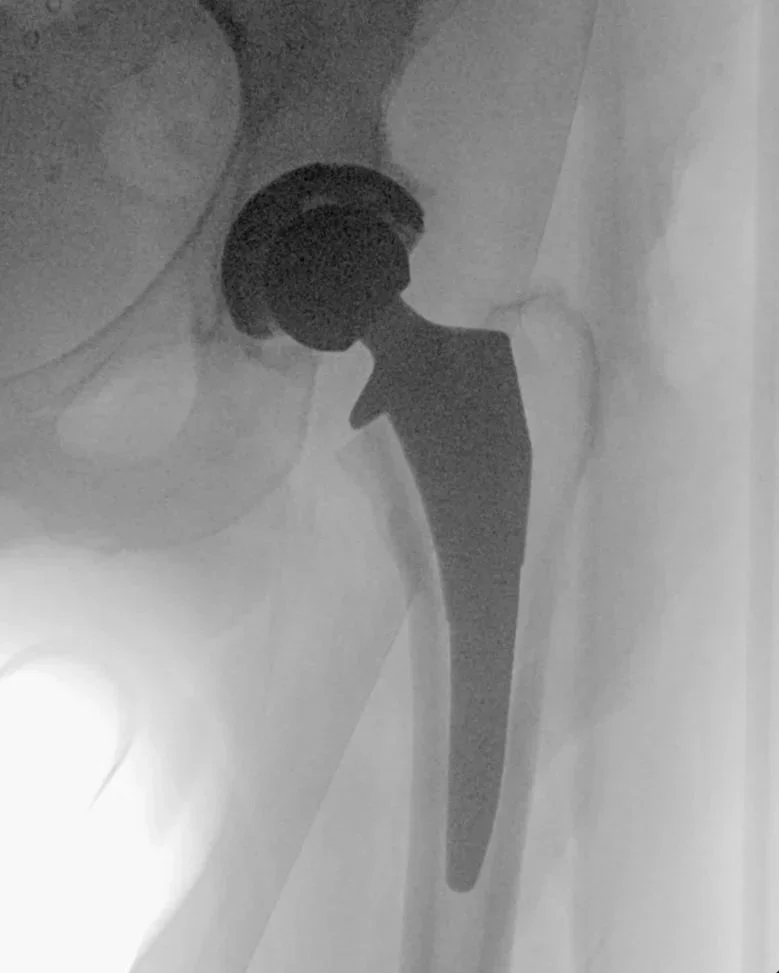

Hip replacement prosthesis demonstrating joint reconstruction for arthritis pain relief.

Clinical Outcomes